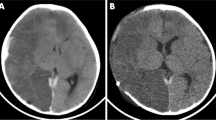

The stepwise treatment protocol of increased ICP at our centre aimed to maintain an ICP of < 20 mmHg similar to the RESCUEicp study by Hutchinson et al. [1]: the initial step comprised head elevation, sedation and analgesia along with normoglycemia, normothermia, normoxemia and the administration of intravenous hyperosmolar solutions. An ICP probe was placed if the patient was unconscious or sedated and intubated. Next, if ICP was not controlled by these measures, sedation was deepened and a ventriculostomy was placed if necessary. Hyperventilation and in some cases mild hypothermia were used if required as a rescue manoeuvre. Barbiturates were not routinely administered, but some patients received thiopental boluses. Finally, if ICP persisted above 20 mmHg, DC was conducted. Four types of craniectomy were used: bifrontal craniectomy with one or two bone flaps, and unilateral or bilateral frontotemporoparietal hemicraniectomy (Fig. 1). The treatment protocol remained unchanged during the study period. The present cohort also includes patients who underwent primary DC, which was conducted upon clinical requirement immediately after admission to OUH.

Three-dimensional computed tomography reconstructions of the four types of decompressive craniectomy performed in our centre. A depicts a bifrontal two-flap craniectomy, B a bifrontal one-flap craniectomy, C a unilateral frontotemporoparietal hemicraniectomy and D a bilateral hemicraniectomy. In B, dural osteogenesis is seen at the craniectomy defect site (scan taken 2 months after DC)

In total, 24 patients underwent DC at a median age of 16.0 years (IQR 1.2, range 7.5 to 17.7). The mean follow-up time was 4.2 years (SD 3.6, range 0 days to 10.3 years). The primary diagnoses were TBI in 20 cases (83%), ischemic stroke in two (8%), encephalitis in one (4%) and spontaneous intracranial haemorrhage in one (4%). The median initial GCS was 5.0 (IQR 5.0). Thirteen (65%) of the TBI cases were due to motor vehicle accidents. In TBI patients, the mean Rotterdam CT score in the primary CT scan was 3.0 (SD 1.2, range 1 to 5). DC was conducted at mean 1.6 days (SD 1.6, range 0 to 7 days) after the primary insult—six (25%) craniectomies were primary and 18 (75%) secondary/delayed. The mean size of the craniectomy was 103 cm2 (SD 19, range 76 to 147 cm2). Six (25%) of the craniectomies were bifrontal one-flap, five (21%) bifrontal two-flap, 12 (50%) unilateral hemicraniectomies and one (4%) bilateral hemicraniectomy (Fig. 1). Baseline characteristics of the DC patients are reported in more detail in Table 1. All the patients with reliable preoperative ICP data (n = 7) had a maximum ICP of > 25 mmHg, and the ICPs remained > 20 mmHg for mean 3.4 h (SD 3.0, range 0.24 to 7.95 h) during the last 8 h before DC. See Supplementary Fig. 1 and Supplementary Table 1 for a description of preoperative ICP courses.